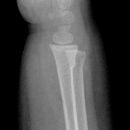

Hand / Handgelenk